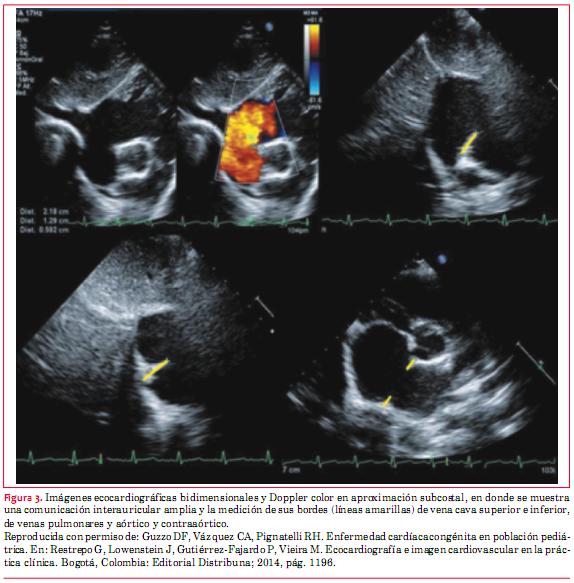

Finalmente resulta de importancia medir los bordes del defecto con miras a su oclusión mediante dispositivos. Los mismos deben medir por lo menos 5 mm(13) y debe realizarse esta medición respecto a varias estructuras circundantes a saber: VCS, VCI, venas pulmonares, mitral, aórtico y contraaórtico (figura 3)(14).

1. Guzzo DF, Vázquez CA, Pignatelli RH. Enfermedad cardíaca congénita en población pediátrica. En: Restrepo G, Lowenstein J, Gutiérrez-Fajardo P, Vieira M. Ecocardiografía e imagen cardiovascular en la práctica clínica. Bogotá, Colombia: Editorial Distribuna; 2014. p. 1194.

14. Guzzo DF, Vázquez CA, Pignatelli RH. Enfermedad cardíaca congénita en población pediátrica. En: Restrepo G, Lowenstein J, Gutiérrez-Fajardo P, Vieira M. Ecocardiografía e imagen cardiovascular en la práctica clínica. Bogotá, Colombia: Editorial Distribuna, 2014; p. 1196